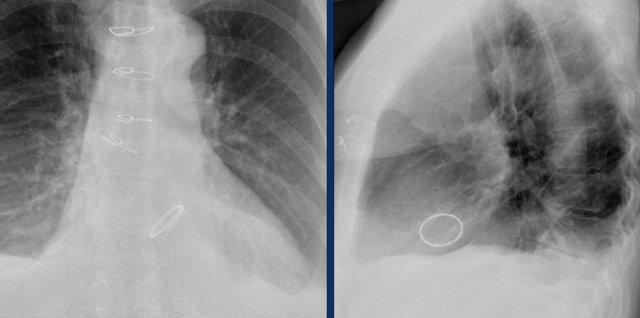

Đây là ví dụ về một ICD với các điện cực đặt tại tiểu nhĩ phải, mỏm thất phải và một điện cực đến thất trái qua tĩnh mạch vành sau.

Có thể nhận biết hai cuộn sốc điện của ICD dưới dạng các dải trắng dày hơn dọc theo đường đi của điện cực.

Đây là hình ảnh máy tạo nhịp hai thất với ba điện cực.

Điện cực tạo nhịp nhĩ phải nằm ở tiểu nhĩ phải.

Điện cực này đi xuống dưới vào nhĩ phải trước, sau đó vòng lên trên và ra trước, nơi nó được neo chặt vào các bè cơ của tiểu nhĩ.

Điện cực thất trái đi qua nhĩ phải và xoang vành, cuối cùng được đặt ở phía sau vào một tĩnh mạch tim bên trái.